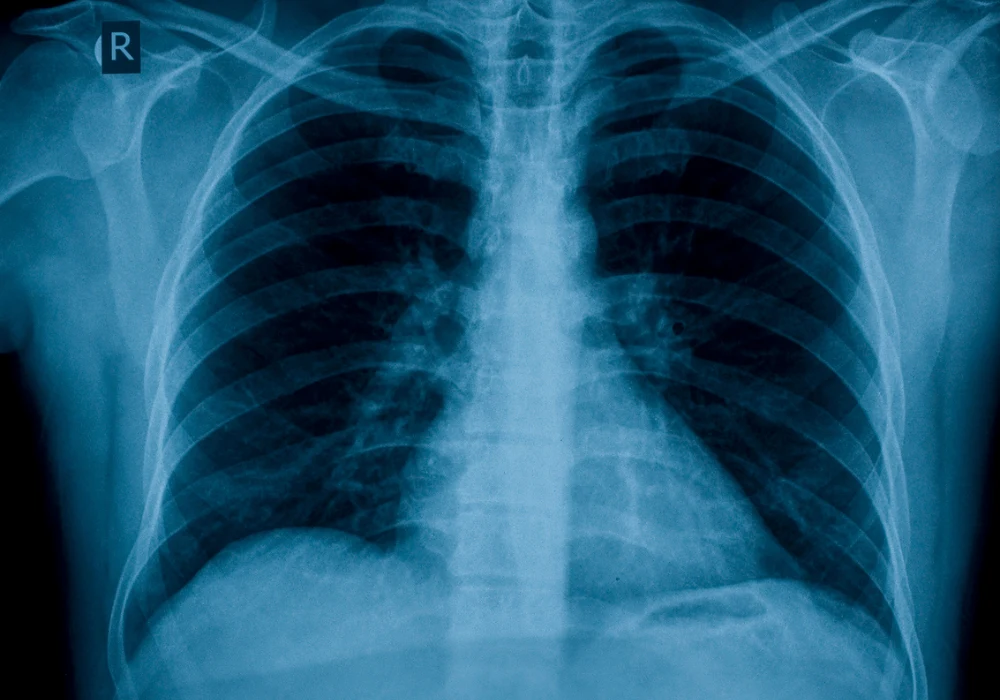

GPT-4 ADA’s Application in Chest Radiograph Evaluation

In a recent study, researchers assessed GPT-4 ADA’s performance on a dataset of bedside chest radiographs from University Hospital RWTH Aachen. The model was tasked with various analytical functions, including plotting radiograph usage trends, performing descriptive statistical analyses and setting up predictive models to identify pulmonary opacities. The study involved 43,788 chest radiograph reports, accompanied by demographic and laboratory data from patients in intensive care, creating a complex dataset that would typically demand advanced technical expertise to analyse effectively.

GPT-4 ADA autonomously executed these tasks, generating insights comparable to those developed by specialist models. The AI model was able to visualise radiograph usage trends over time and determine statistical associations within the dataset, providing both descriptive and quantitative insights. For predictive modelling, GPT-4 ADA implemented gradient boosting techniques and logistic regression models to forecast pulmonary opacity occurrences, achieving an area under the curve (AUC) of 0.75, closely matching the 0.80 AUC achieved by human specialists.

Despite minor statistical inaccuracies, GPT-4 ADA demonstrated consistency and reliability in its outputs, offering radiologists an accessible tool for robust data analysis. Researchers validated the AI-driven analyses, which were largely accurate, with performance metrics, such as sensitivity and specificity, comparable to those produced by experts. Notably, GPT-4 ADA’s output accuracy was maintained even when operating without explicit guidance, highlighting its potential for autonomous analysis in real-world settings where clinician involvement might be limited.